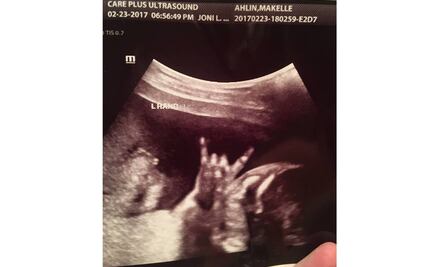

Ultrasonido muestra a "bebé listo para rockear"; imagen se hace viral

Makelle Ahlin y su esposo Jared, de Utah, publicaron en Facebook la imagen de un ultrasonido que muestra al feto haciendo lo que parece ser la característica seña del rock ‘n’ roll; la imagen se ha viralizado